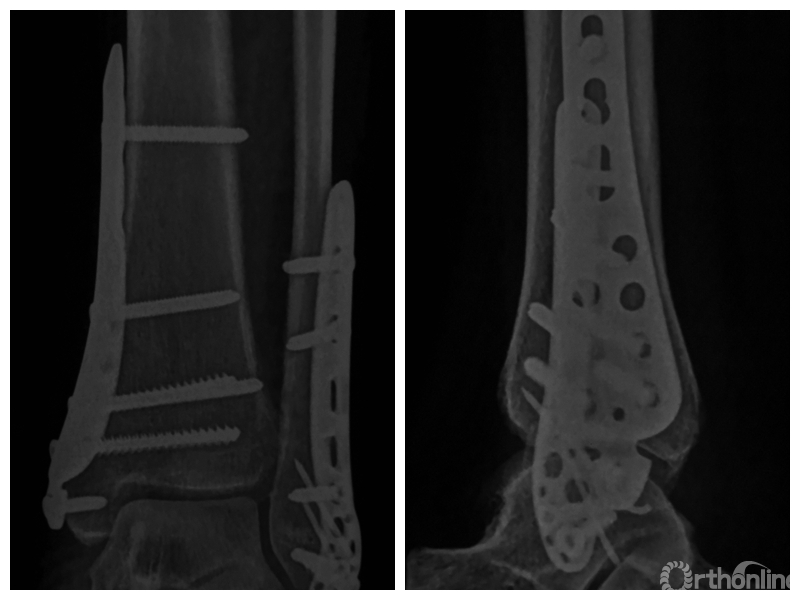

图1 支撑钢板固定组患者,女,63岁,右侧旋后-内收型II度踝关节骨折 a. 术前正侧位X线片;b. 术前CT;c. 术后2周正侧位X线片;d. 术后2年正侧位X线片

图1c 术后2周正侧位X线片

两组患者均获随访,支撑钢板固定组随访时间46~91,平均64.5个月;螺钉固定组随访时间44~86,平均59.5个月。支撑钢板固定组患者术后完全负重时间为(11.5±1.6)周,较螺钉固定组的(12.6±2.3)周显著缩短,比较差异有统计学意义(t=2.05,P=0.04)。X线片复查示,支撑钢板组均获解剖复位,均达愈合;螺钉固定组有20例获解剖复位,2例畸形愈合,1例不愈合,支撑钢板组骨折愈合时间为(11.5±1.6)周,螺钉固定组为(12.0±1.7)周,比较差异无统计学意义(t=1.06,P=0.30)。见图1、2。支撑钢板固定组3例(10%)、螺钉固定组4例(17.4%)发生创伤性关节炎,均采取保守治疗;两组比较差异无统计学意义(P=0.45)。